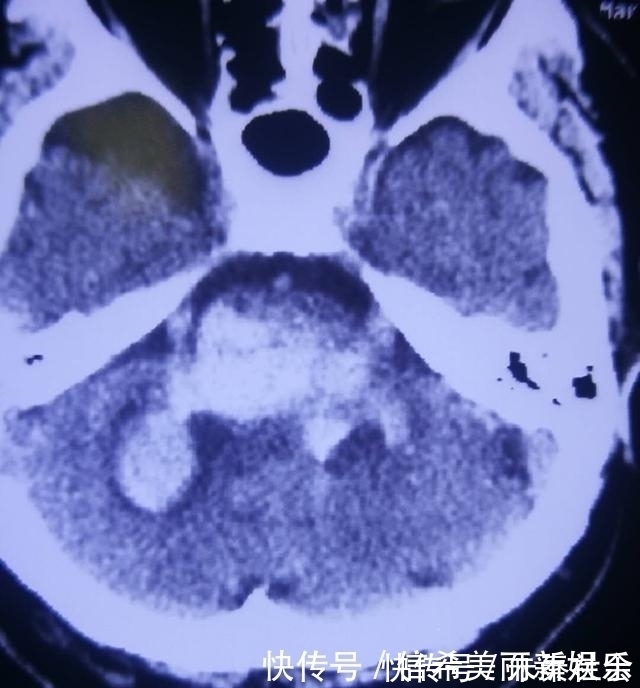

医生看着这位孝顺的儿子回答道:“你的父亲是脑干出血,并且出血量达到10毫升以上了,开始来的时候,和你沟通考虑可以手术,但是位置太重要,手术的风险很大,你签字保守治疗。”

医生无奈的看着他说:“这几天和你说了,这个部位很重要,出血的部位是呼吸循环中枢,现在患者脱不下呼吸机,心率快,同时又中枢高热,已经出现肾功能不全的并发症,一周还是脑水肿最严重的时候,所以现在还很危险。至于什么时候能脱离风险?大多数是半个月左右,但是也要根据患者病情来看,有的病情重的也许一个月还是这样。”